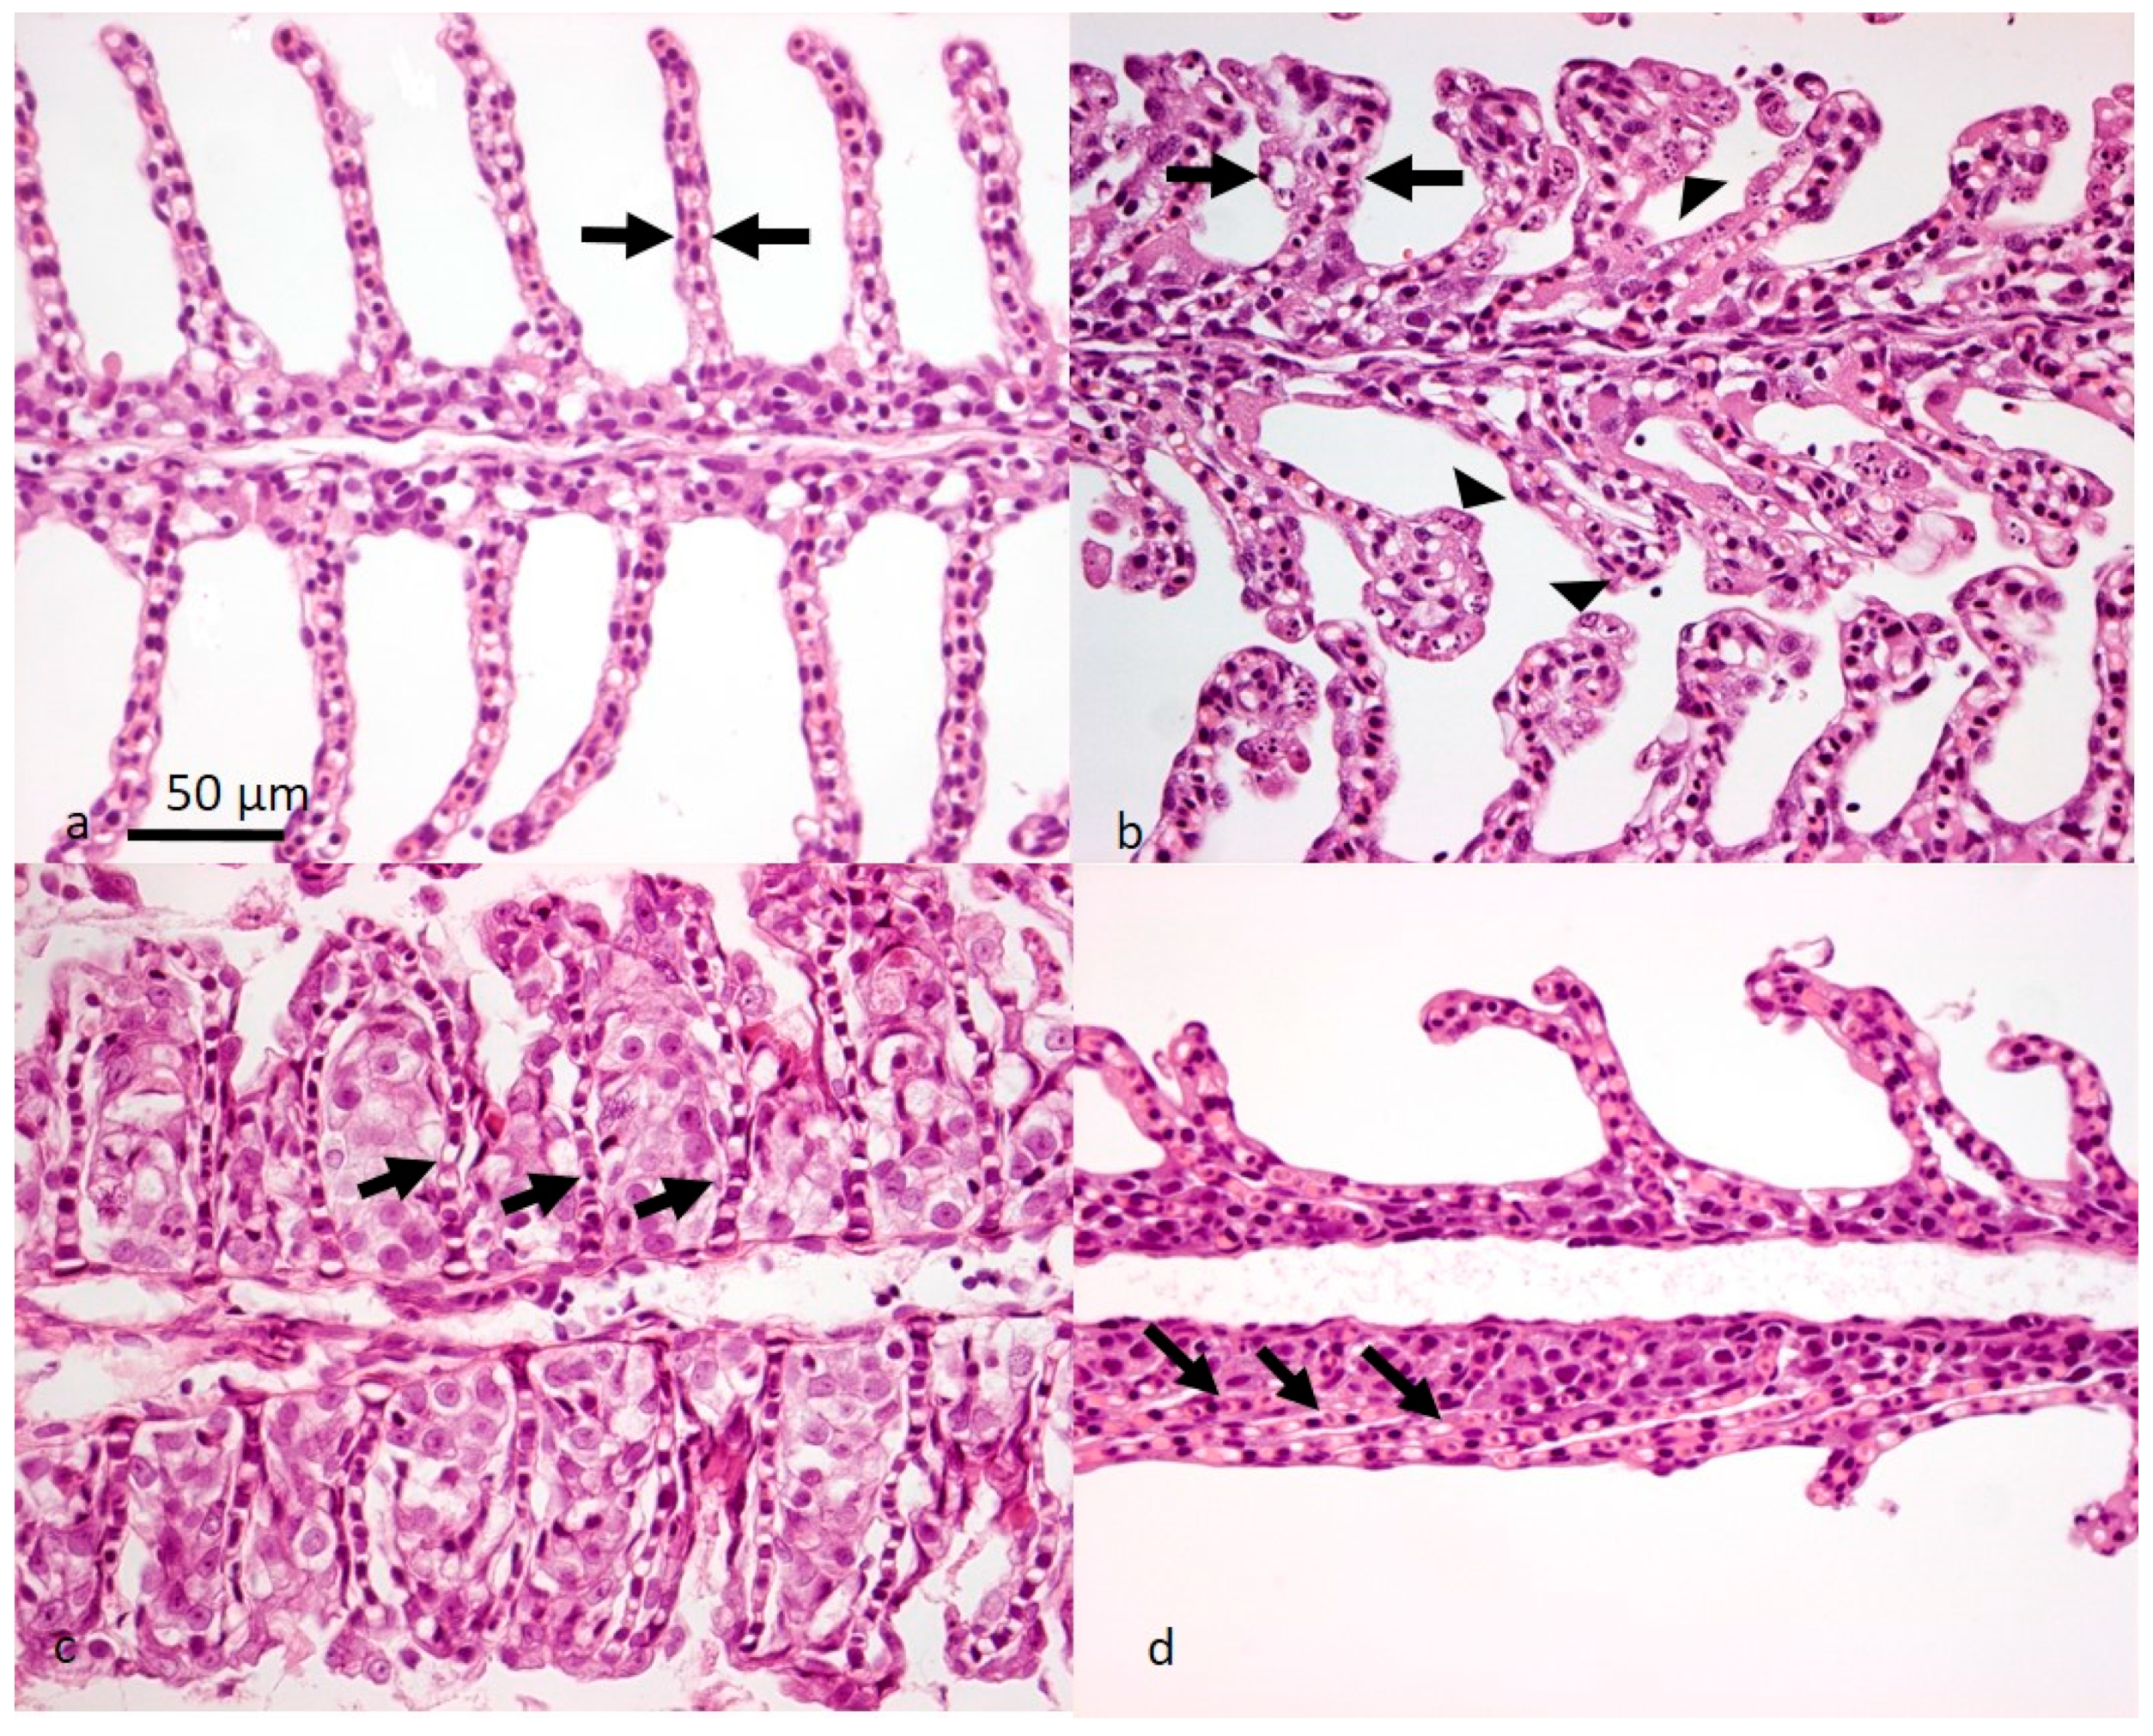

- Gjessing, M.C.; Thoen, E.; Tengs, T.; Skotheim, S.A.; Dale, O.B. Salmon gill poxvirus, a recently characterized infectious agent of multifactorial gill disease in freshwater- and seawater-reared Atlantic salmon. J. Fish Dis. 2017, 40, 1253–1265. [Google Scholar] [CrossRef]

- Gjessing, M.C.; Christensen, D.H.; Manji, F.; Mohammad, S.; Petersen, P.E.; Saure, B.; Skjengen, C.; Weli, S.C.; Dale, O.B. Salmon gill poxvirus disease in Atlantic salmon fry as recognized by improved immunohistochemistry also demonstrates infected cells in non-respiratory epithelial cells. J. Fish Dis. 2018, 41, 1103–1110. [Google Scholar] [CrossRef]